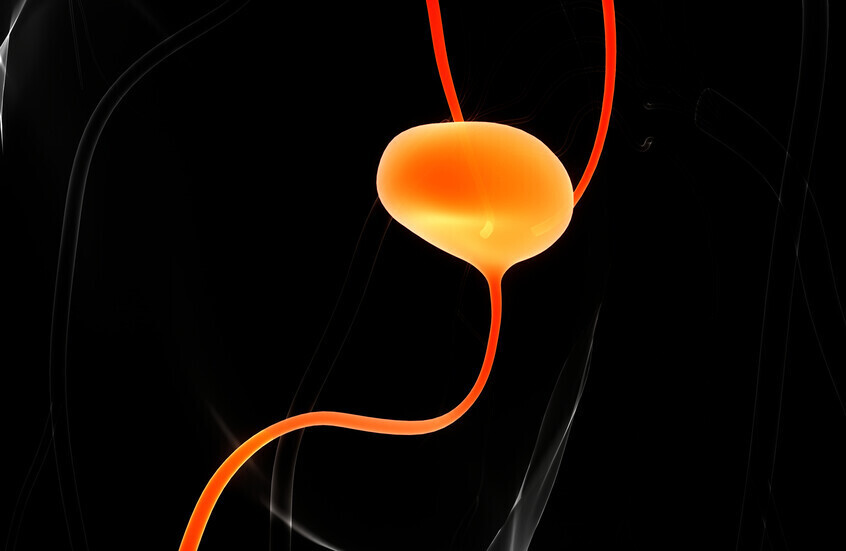

علاج ثوري يمحو الأورام تماما لدى معظم مرضى سرطان المثانة

أعلن باحثون عن نجاح نظام دوائي جديد في القضاء التام على الأورام لدى 82% من مرضى سرطان المثانة عالي الخطورة، الذين فشلت علاجاتهم السابقة.

وفي معظم الحالات، اختفى السرطان تماما في غضون ثلاثة أشهر من بدء العلاج، وظل ما يقارب نصف المرضى خالين تماما من المرض بعد مرور عام.

ويعد هذا الإنجاز نقلة نوعية في مواجهة أحد أكثر أنواع السرطان شيوعا. ويأتي النظام العلاجي المسمى TAR-200 على شكل معجنات البريتزل، ويحتوي على دواء جيمسيتابين، وهو دواء للعلاج الكيميائي. ويتم إدخال هذا الجهاز الدوائي صغير الحجم إلى المثانة عبر قسطرة، ويطلق الدواء لمدة ثلاثة أسابيع لكل دورة علاجية، على عكس الطريقة التقليدية التي كان فيها الدواء يبقى لبضع ساعات فقط.

ويشرح الدكتور سيا دانشمند، قائد الفريق البحثي من مركز كيك الطبي: "اكتشفنا أن بقاء الدواء لفترة أطول داخل المثانة يسمح له باختراق أعمق للأنسجة وتدمير أكبر للخلايا السرطانية. وهذه الطريقة في الإطلاق البطيء أثبتت تفوقا كبيرا على الأساليب التقليدية".

وشملت الدراسة العالمية 85 مريضا من 144 مركزا طبيا حول العالم، جميعهم كانوا يعانون من سرطان المثانة غير العضوي عالي الخطورة الذي لم يستجب للعلاج المناعي القياسي. وكان الخيار الوحيد المتبقي لهؤلاء المرضى هو الاستئصال الجراحي الكامل للمثانة، وهي عملية خطيرة تهدد جودة حياتهم.

وبعد خضوع المرضى للعلاج الجديد كل ثلاثة أسابيع لمدة ستة أشهر، تلاه علاجات دورية لمدة عامين، اختفت الأورام تماما لدى 70 مريضا في غضون ثلاثة أشهر، وظل 50% منهم خالين من المرض بعد مرور عام كامل. والأهم من ذلك، أن الآثار الجانبية كانت طفيفة مقارنة بالعلاجات الأخرى.

كما وجد الباحثون أن الجمع بين TAR-200 ودواء مناعي آخر (cetrelimab) كان أقل فعالية وتسبب في المزيد من الآثار الجانبية مقارنة بـ TAR-200 وحده.

وسيستمر مراقبة المشاركين في الدراسة لمدة عام آخر، ولكن تم إغلاق باب التسجيل الآن.

ويؤكد الباحثون أن هذا النجاح يفتح آفاقا جديدة في علاج السرطان بالإطلاق الدوائي البطيء، ما يعزز الأمل في تطوير علاجات أكثر فاعلية وأقل ضررا للمرضى حول العالم.

نشرت الدراسة في مجلة Journal of Clinical Oncology.